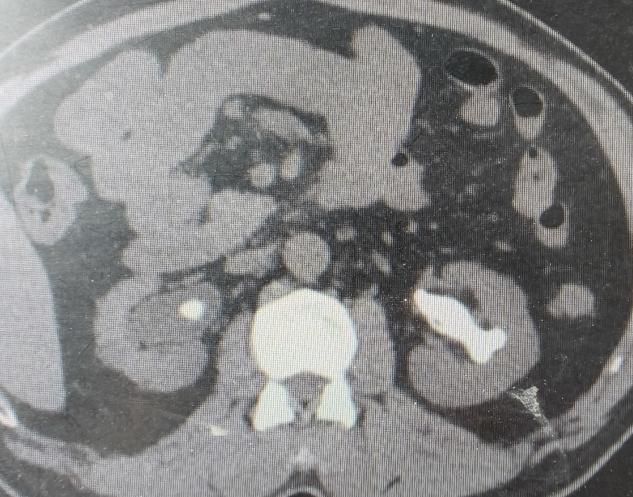

许多年前的一次体检,朱先生得知自己患有双肾结石。因当时症状不明显,也未规律复查。时间一晃而过。近期,朱先生时常感到腰部隐隐酸胀,体力也大不如前。他原以为是年纪大了的正常现象,直到一次剧烈的腰痛发作,才在家人的催促下就医,检查结果让他和家人都大吃一惊。CT显示,他的双肾结石,其中左肾几乎填满了各个肾盏,合并积水及感染,并且明确糖尿病,血糖超高。

“就像一个模具里灌满了石膏,结石完全依照肾脏内部的空腔形状生长,处理起来非常棘手。”泌尿外科主任、副主任医师刘伟光介绍,“尤其朱先生还有糖尿病,这大大增加了手术的复杂性和感染风险。”

经过全面的评估和多学科会诊,泌尿外科团队为朱先生制定了周密的“两步走”微创手术方案,分期行双侧经皮肾镜取石术(同步控制血糖及治疗感染)。

· 第一步:攻坚右肾(存在积水的首先处理)。 在超声精确定位下,泌尿外科团队建立了仅铅笔粗细的微通道,利用高效的碎石设备,将右肾内坚硬的“石头城堡”逐步击碎、取出。手术顺利,手术后恢复良好。

· 第二步:清理左肾。 待右肾稳定恢复后,泌尿外科团队为左肾实施了取石手术。左侧结石更巨大、更复杂,手术团队凭借丰富的经验,再次成功完成“清剿”。

术后复查影像显示,朱先生的双侧肾脏结石已完全取净,肾积水消失。困扰朱先生多年的“石头包袱”,终于被彻底卸下。